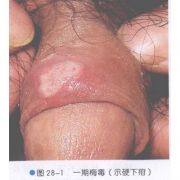

| 2021年7月26日 (一) 20:03 | 一期梅毒.jpg (文件) |  |

158 KB | Uploaded with SimpleBatchUpload | 3 |